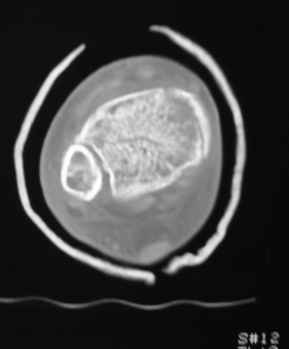

Остеопороз (продолжение 3) - данные КТ

Продолжая тему представляю данные КТ нашей пациентки.

Вопросы к сообществу - в сообщении №2.

Юрий Алексеевич Булахтин